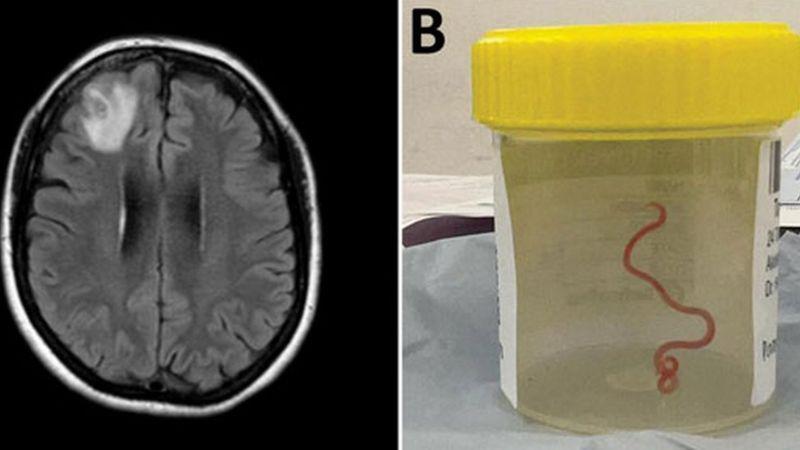

Médicos australianos hallaron por primera vez un gusano de 8 centímetros en el cerebro de una mujer de 64 años. El parásito fue retirado “vivo y coleando” del cerebro de la mujer cuando le estaban realizando una biopsia por “olvidos y depresión”. Según investigadores estas especies son comunes en canguros y pitones diamantina pero no en humanos.

Los médicos se encontraban realizando una resonancia magnética a la paciente y notaron una “lesión atípica” en el frente de su cerebro.

En las imágenes descubrieron que, dentro de su cerebro, había un gusano de ocho centímetros llamada Ophidascaris Robertsi. La doctora Sanjaya Senanayake, que también es profesora asociada de medicina de la Universidad Nacional de Australia (ANU), le dijo a la BBC que el caso es una advertencia y agregó que el equipo de la ANU informó que en los últimos 30 años aparecieron 30 nuevos tipos de infecciones.